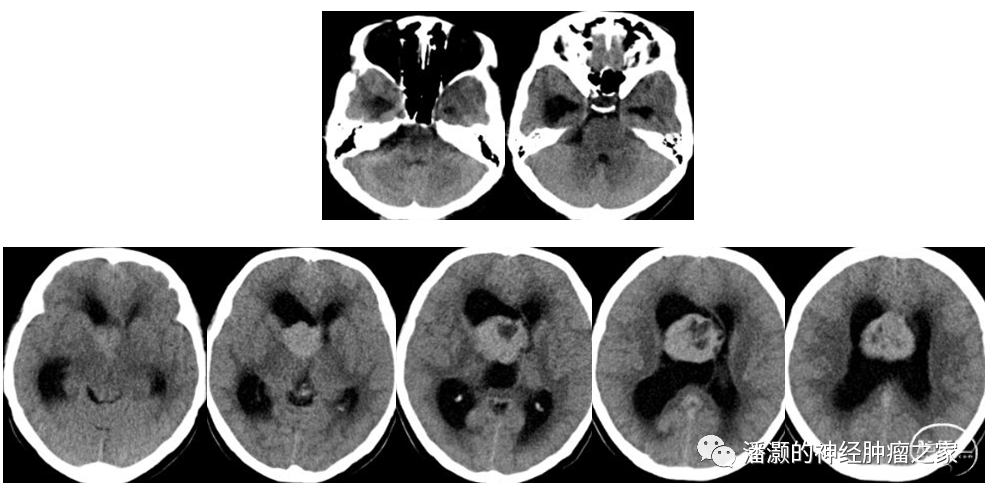

患者女性,30岁,主诉为头痛头晕2月。入院查体:行走不稳,肌力肌张力正常,余神经系统无特殊。入院辅助检查:右侧脑室占位、右侧桥小脑角区占位。

术前影像如下:

CT提示右侧CP角低密度占位,右侧脑室额角为主等低密度混杂占位,幕上脑室系统扩大。